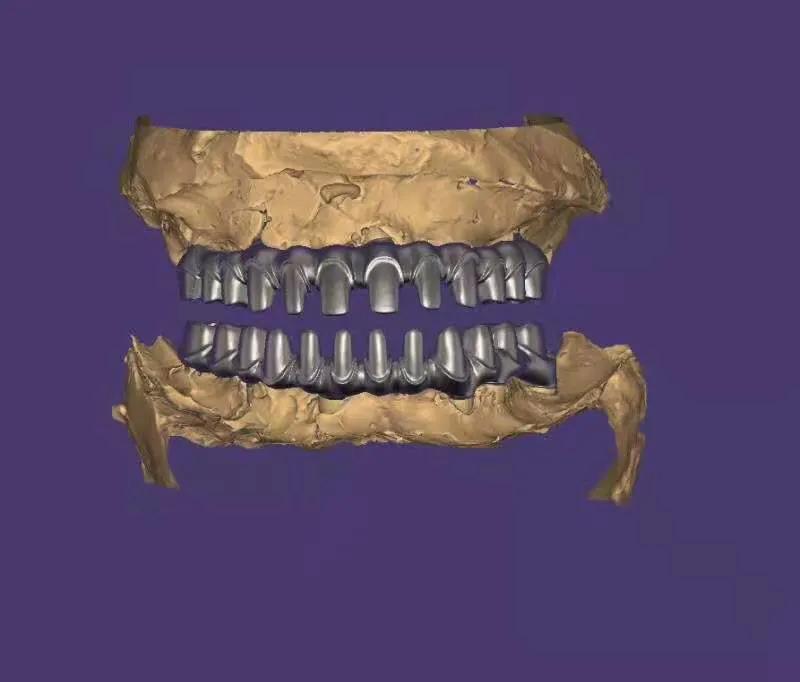

典型的負(fù)重,All-On-4。

這就是傳說中的當(dāng)天戴牙當(dāng)天吃飯,網(wǎng)上到處宣傳的就是這種種植方法。但是不是每一個(gè)人都能做這個(gè),All-on-4一般需要預(yù)約,醫(yī)生種植完畢,技師馬上開始取模做牙,大概5小時(shí)左右就可以戴上臨時(shí)牙回家吃飯了,休息一兩天,正常吃飯是沒問題的。

3. 有些患者以為一顆牙也可以這樣,一顆是不行的,至少連續(xù)4顆才可以,比如門牙連續(xù)4顆就可以做。